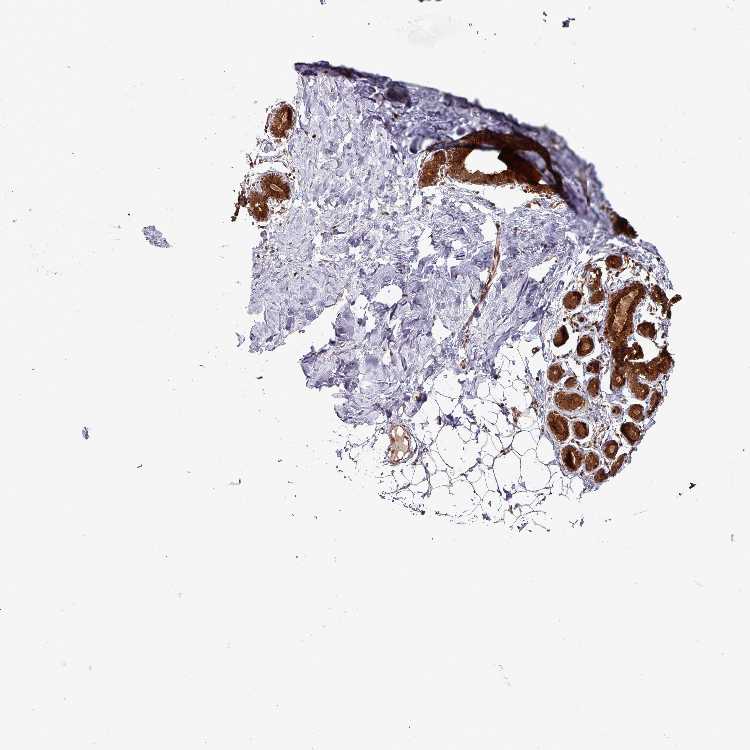

BREAST - Antibody stainingi

Antibody staining in the annotated cell types in the current human tissue is reported as not detected, low, medium, or high, based on conventional immunohistochemistry profiling in selected tissues. This score is based on the combination of the staining intensity and fraction of stained cells.

Each image is clickable and will lead to virtual microscopy that enables deeper exploration of all samples and also displays staining intensity scores, fraction scores and subcellular localization as well as patient and tissue information for each sample.

Antibody HPA053164

Adipocytes Low

Glandular cells High

Myoepithelial cells High